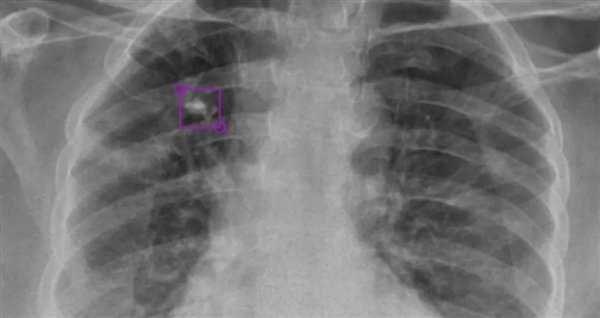

NVIDIA AI印度助力:通過X射線診斷肺結(jié)核

DeepTek希望通過AI驅(qū)動(dòng)的放射平臺(tái),大大提升全球在醫(yī)學(xué)影像診斷領(lǐng)域的能力,為此開發(fā)了全新的DxTB工具,用來篩查肺結(jié)核的X射線圖像,并標(biāo)記病例,以供醫(yī)學(xué)專家進(jìn)行優(yōu)先檢查。

DeepTek AI模型檢測到的右上葉肺部鈣化結(jié)節(jié)

由于放射科醫(yī)師通常會(huì)花更多時(shí)間進(jìn)行CT或MRI掃描檢查,能夠讀取X射線掃描的成像專家十分短缺,因此AI可以發(fā)揮重要作用。